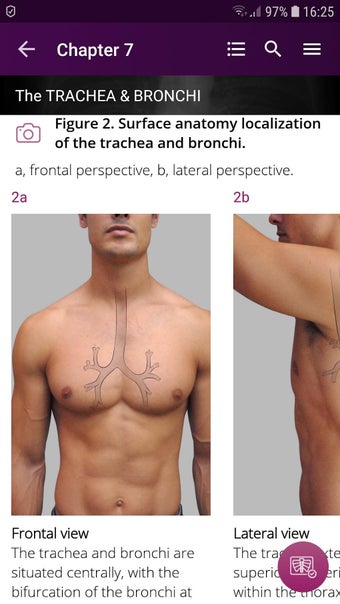

Radioloji'yi Keşfet: Göğüs Röntgeni Yorumlama, göğüs röntgeninin yorumlanmasının anlaşılmasını artırmak için tasarlanmış bir eğitim uygulamasıdır ve doktorlar, tıp öğrencileri ve radyologlar tarafından kullanılması amaçlanmaktadır. Uygulama, en küçük detayları görüntülemek için yakınlaştırılabilecek yüksek kaliteli görüntüler ve her bulgunun önemini anlamanıza yardımcı olacak bir sesli yorum içerir.

Uygulamanın amacı, kullanıcıların farklı x-ışını bulgularını ve bunların bir hastalığın teşhisinde nasıl kullanılabileceğini daha iyi anlamalarına yardımcı olmaktır. Uygulama, göğüs röntgeni yorumlaması için gerekli çeşitli yapı taşlarını kapsayan 5 bölüme ayrılmıştır.